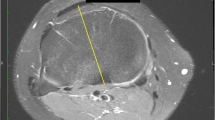

Each person reviewing the MRI scans first identified the femoral TEA using the image that he thought best depicted the medial and lateral femoral epicondyles. The medial epicondyle was defined as the center of the medial sulcus if one was present, or was defined as the peak of the medial epicondyle if a sulcus was not present. The axis was established by drawing a line through the centers of the epicondyles. The TEA then was projected distally onto the tibial images that were to be evaluated. The femoral TEA served as a reference axis for the tibial axes measured in this study.

On the tibial side, each evaluator created three axes: the axis across the greatest medial to lateral width of the tibial plateau (ML), the posterior tibial condylar axis (PC), and the axis perpendicular to the line connecting the midpoint of the greatest mediolateral dimension of the tibial slice being evaluated to the medial 1/3 of the tibial tubercle (TUB) (Figs. 1, 2). Because the tibial tubercle was not always visible on the MR slices evaluated, the patellar tendon was used as a surrogate for the tibial tubercle in these slices. The PCL insertion was not used as the posterior point on this line as the PCL insertion disappears at the more distal resection levels.

The ML dimension of the tibia was characterized as the widest point across the tibial plateau at each resection level. The PC axis was a line formed connecting the posterior margins of the medial and lateral tibial condyles. The axis relative to the patellar ligament insertion was created by first identifying the center point of the ML axis on the tibial plateau and then creating a line to the medial 1/3 mark of the tibial tubercle, or the patellar tendon when the tubercle was not visible on the slice. The TUB axis was the perpendicular to this line. For each observer, 12 data points were collected on each MR image of the knee (three axes at each of four different resection levels), with negative numbers correlating to internal rotation relative to the reference femoral TEA and positive numbers correlating to external rotation.